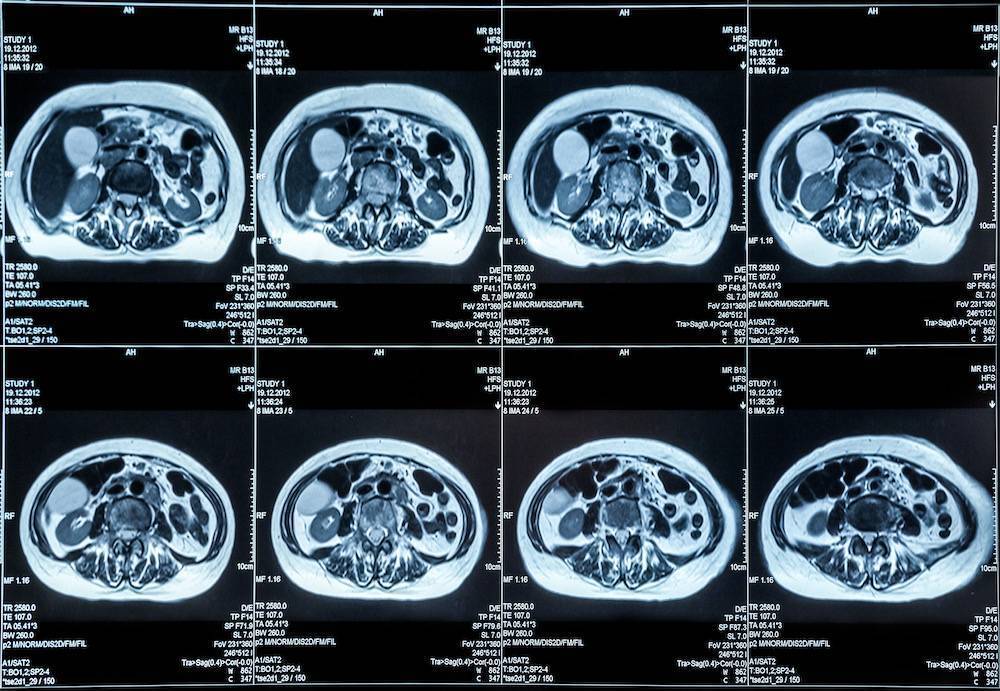

Eine MRT-Bauchuntersuchung kann detaillierte Bilder sowohl des Dick- als auch des Dünndarms liefern. Die bei einer MRT-Untersuchung des Bauchraums eingesetzte Technologie ermöglicht es dem Arzt, das Innere des Bauchraums zu untersuchen, ohne dass Knochen die Sicht behindern.

Eine MRT-Untersuchung des Bauchraums wird durchgeführt, um Organe des Bauchraums wie Nieren, Milz, Leber, Gallenwege, Darm, Bauchspeicheldrüse und Nebennieren zu untersuchen. Bei der Untersuchung werden auch Blutgefäße und Lymphknoten untersucht.

Einige der Erkrankungen, die mit Hilfe einer abdominalen MRT diagnostiziert werden können, sind Tumore im Unterleib, Lebererkrankungen wie Zirrhose oder andere Anomalien der Gallenwege und der Bauchspeicheldrüse.